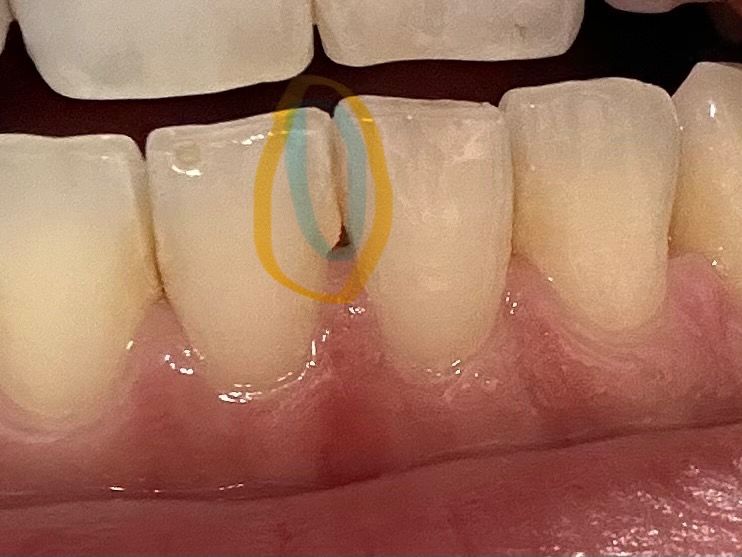

아래 앞니 하얀선과 모양이 옆에 것과 다릅니다

1. 왼쪽 아래앞니 모양이 일자가 아닙니다 ㅜㅜ 이건 이렇게 생긴이빨인걸까요 깨진건가요? 박거나 뭐 그런적이 없습니다. (노란 원)

2. 파란 원 안에 일자로 하얗습니다. 사진 상 잘 안나왔지만 다른 부분에 비해서 너무 하얗게 일자선이 있습니다. ㅠㅠ 이빨이 부식된건가요..?

• 1번 째 사진